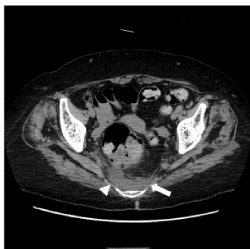

Figure 3. A CT imaging of a homogeneous pattern in the abnormal density area of the presacral area. Case 5. Non-contrast CT at the level of the acetabulum of the hip joint shows an abnormal density area with a homogeneous pattern in the presacral region (arrow). The ventral border was indistinct (arrowhead) and bowl-shaped